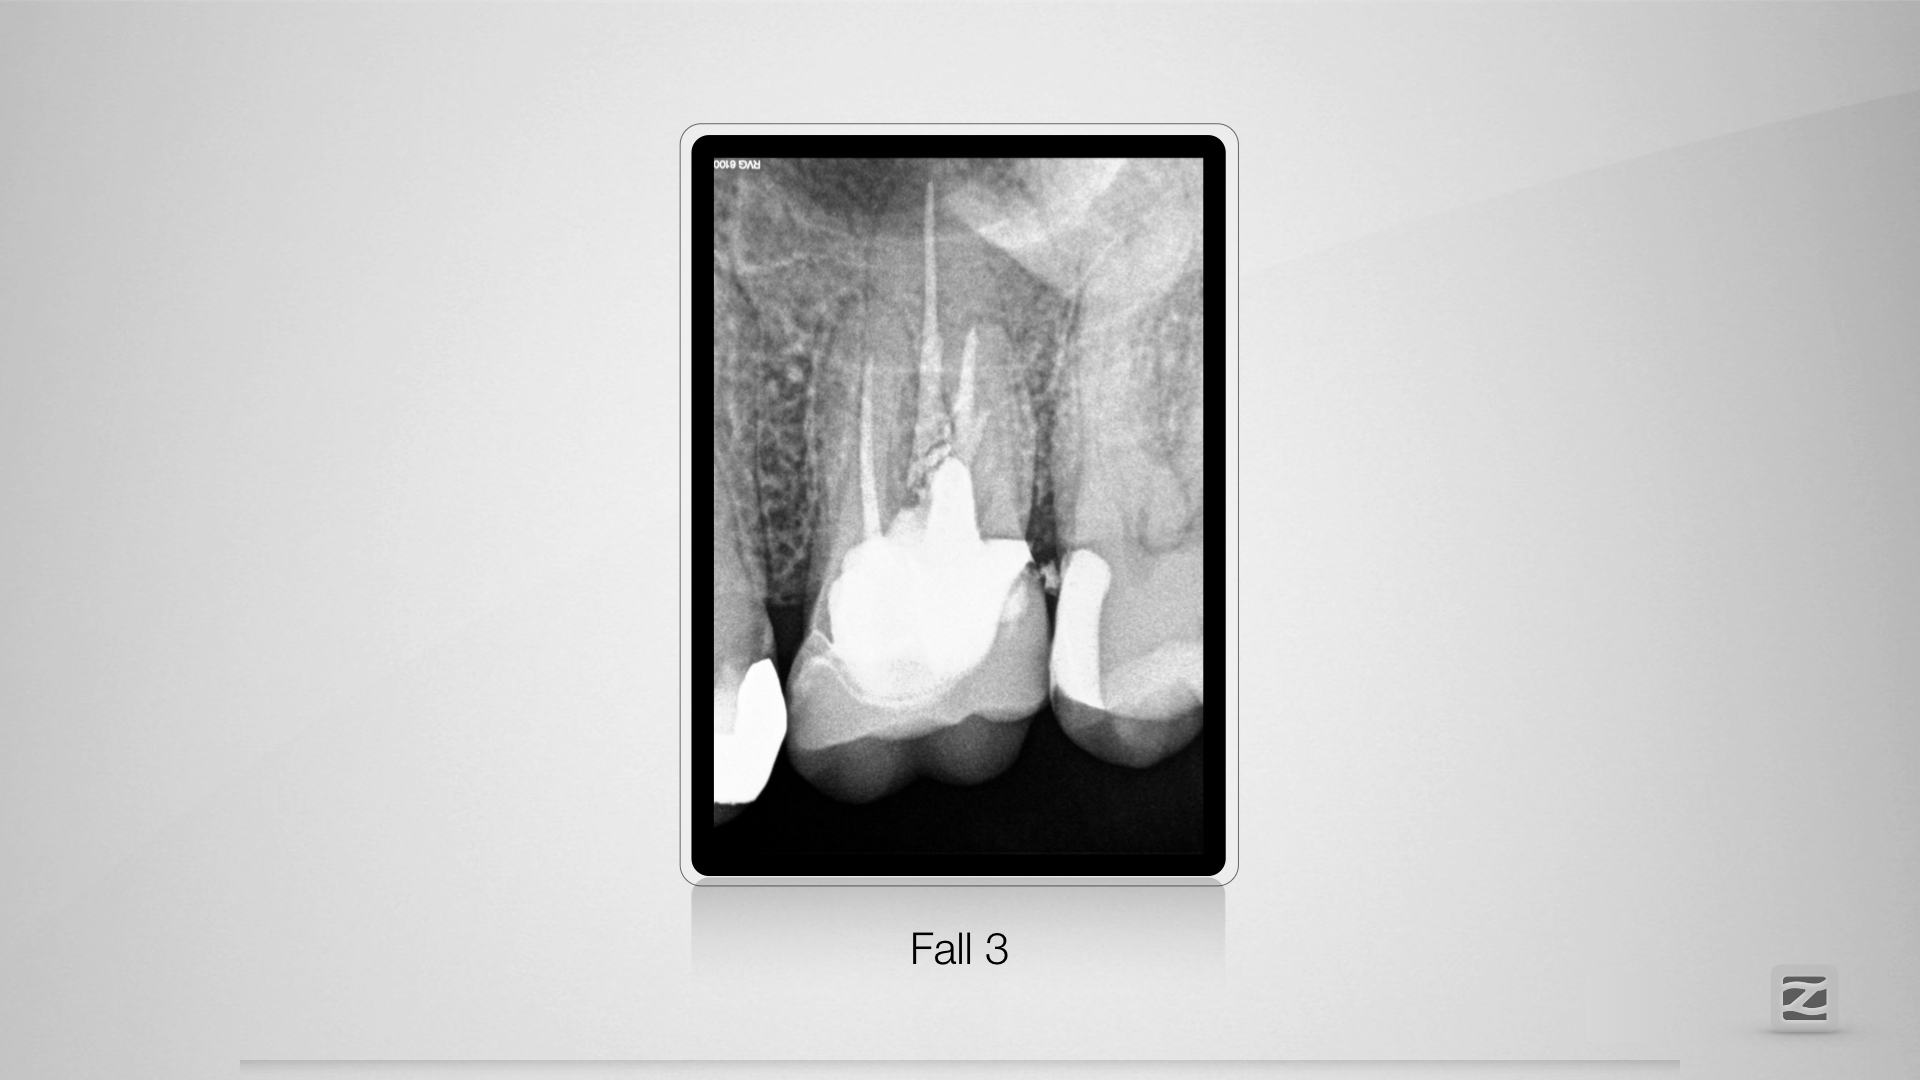

PerforationD.019

Übermut tut selten gut.